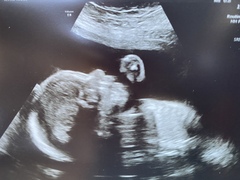

I finally got my 20week re-scan appointment (at 23.5 weeks) but only just!! I rang the hospital yesterday as I hadn’t got a letter or a call, rang at 12 and found out my appointment was for 2pm!! They got to see the last few bits of the heart, but baby made the poor lady (who was training and was specially at the heart part of the training) work for it! Finally got some pics - bubba has a chubby belly ☺️ The blob about the chin is their elbow, they had their had up by their cheek! All is good, we don’t know the sex (we weren’t fussed on finding out to be fair - I know my mindset - not knowing will give me more grit and determination during labour 😂) , but baby also chose to not be in a good position for that as it was! I had to lay on the bed in strange ways just so the could see the one angle of the heart they needed!